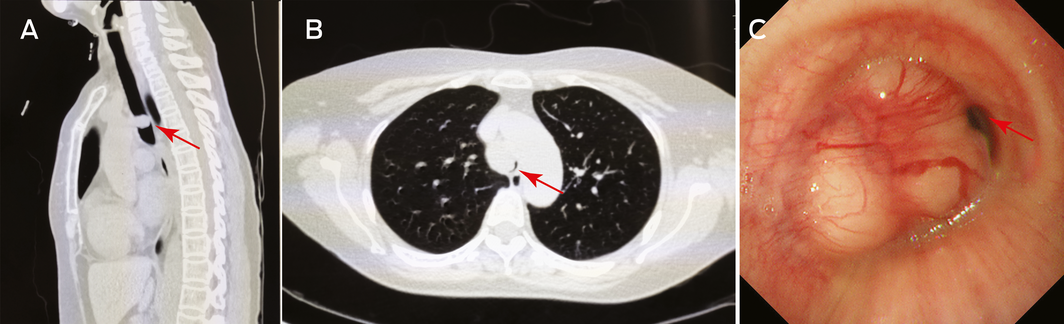

- 1. Karamustafaoglu YA, Yanık F, Yoruk Y. Palliative treatment of recurrent tracheal pleomorphic adenoma 10 years after segmental resection using the endobronchial shaver. Clin Respir J 2020; 14: 495–497.